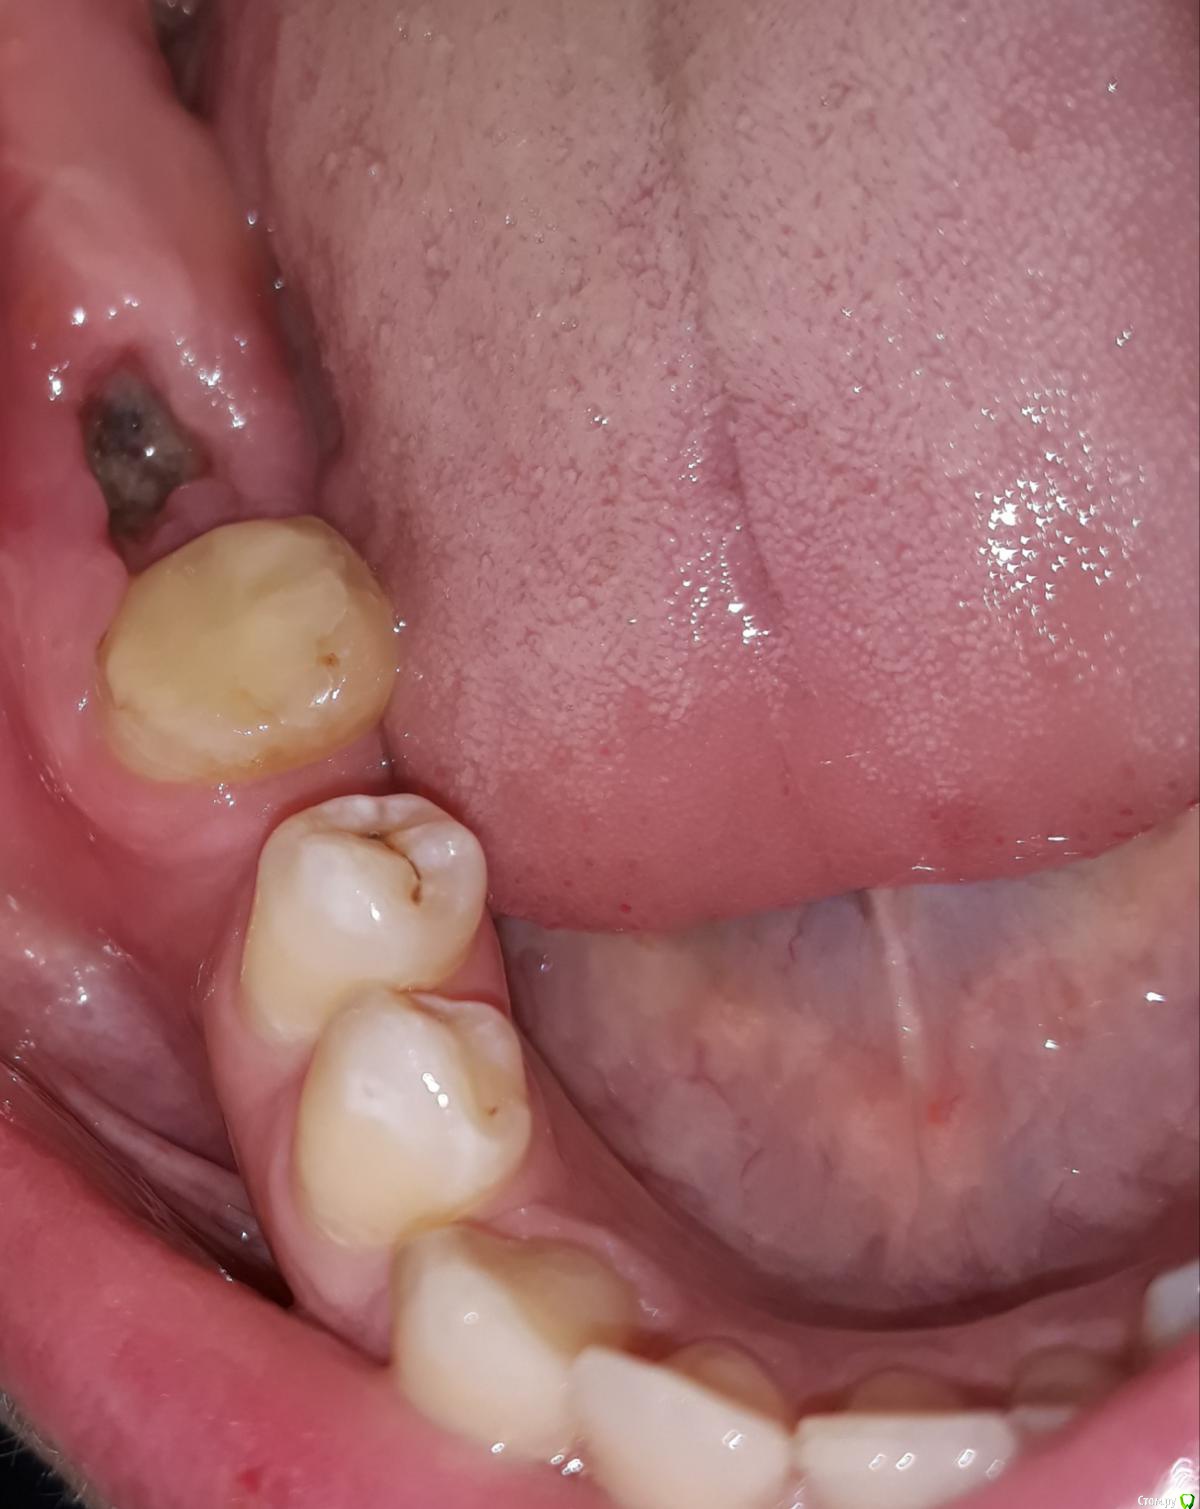

Здравствуйте, уважаемые специалисты, подскажите пожалуйста коронку (металлокерамика) на 47зуб в моем случае лучше ставить на вкладке или на штифте? Один доктор говорит можно и на штифт, а другой что штифтовые конструкции разваливаются за 3-4 года. 48 уже удален. Заранее спасибо за ответ.

Мы не знаем толщину стенок, кроме передней. Теоретически можно и керамический оверлей сделать без вкладок и штифтов.

Коронка у вас все равно обязана держаться, охватывать не штфтовую культю и не вкладку, а сам зуб, и только его. Стало быть, выбирайте для восстановления то, что меньше разрушит зуб, и, как правило, это штифты. Под вкладки надо убирать массу дентина для исключения поднутрений и сглаживания стенок в целях обеспечения пути введения вкладки.